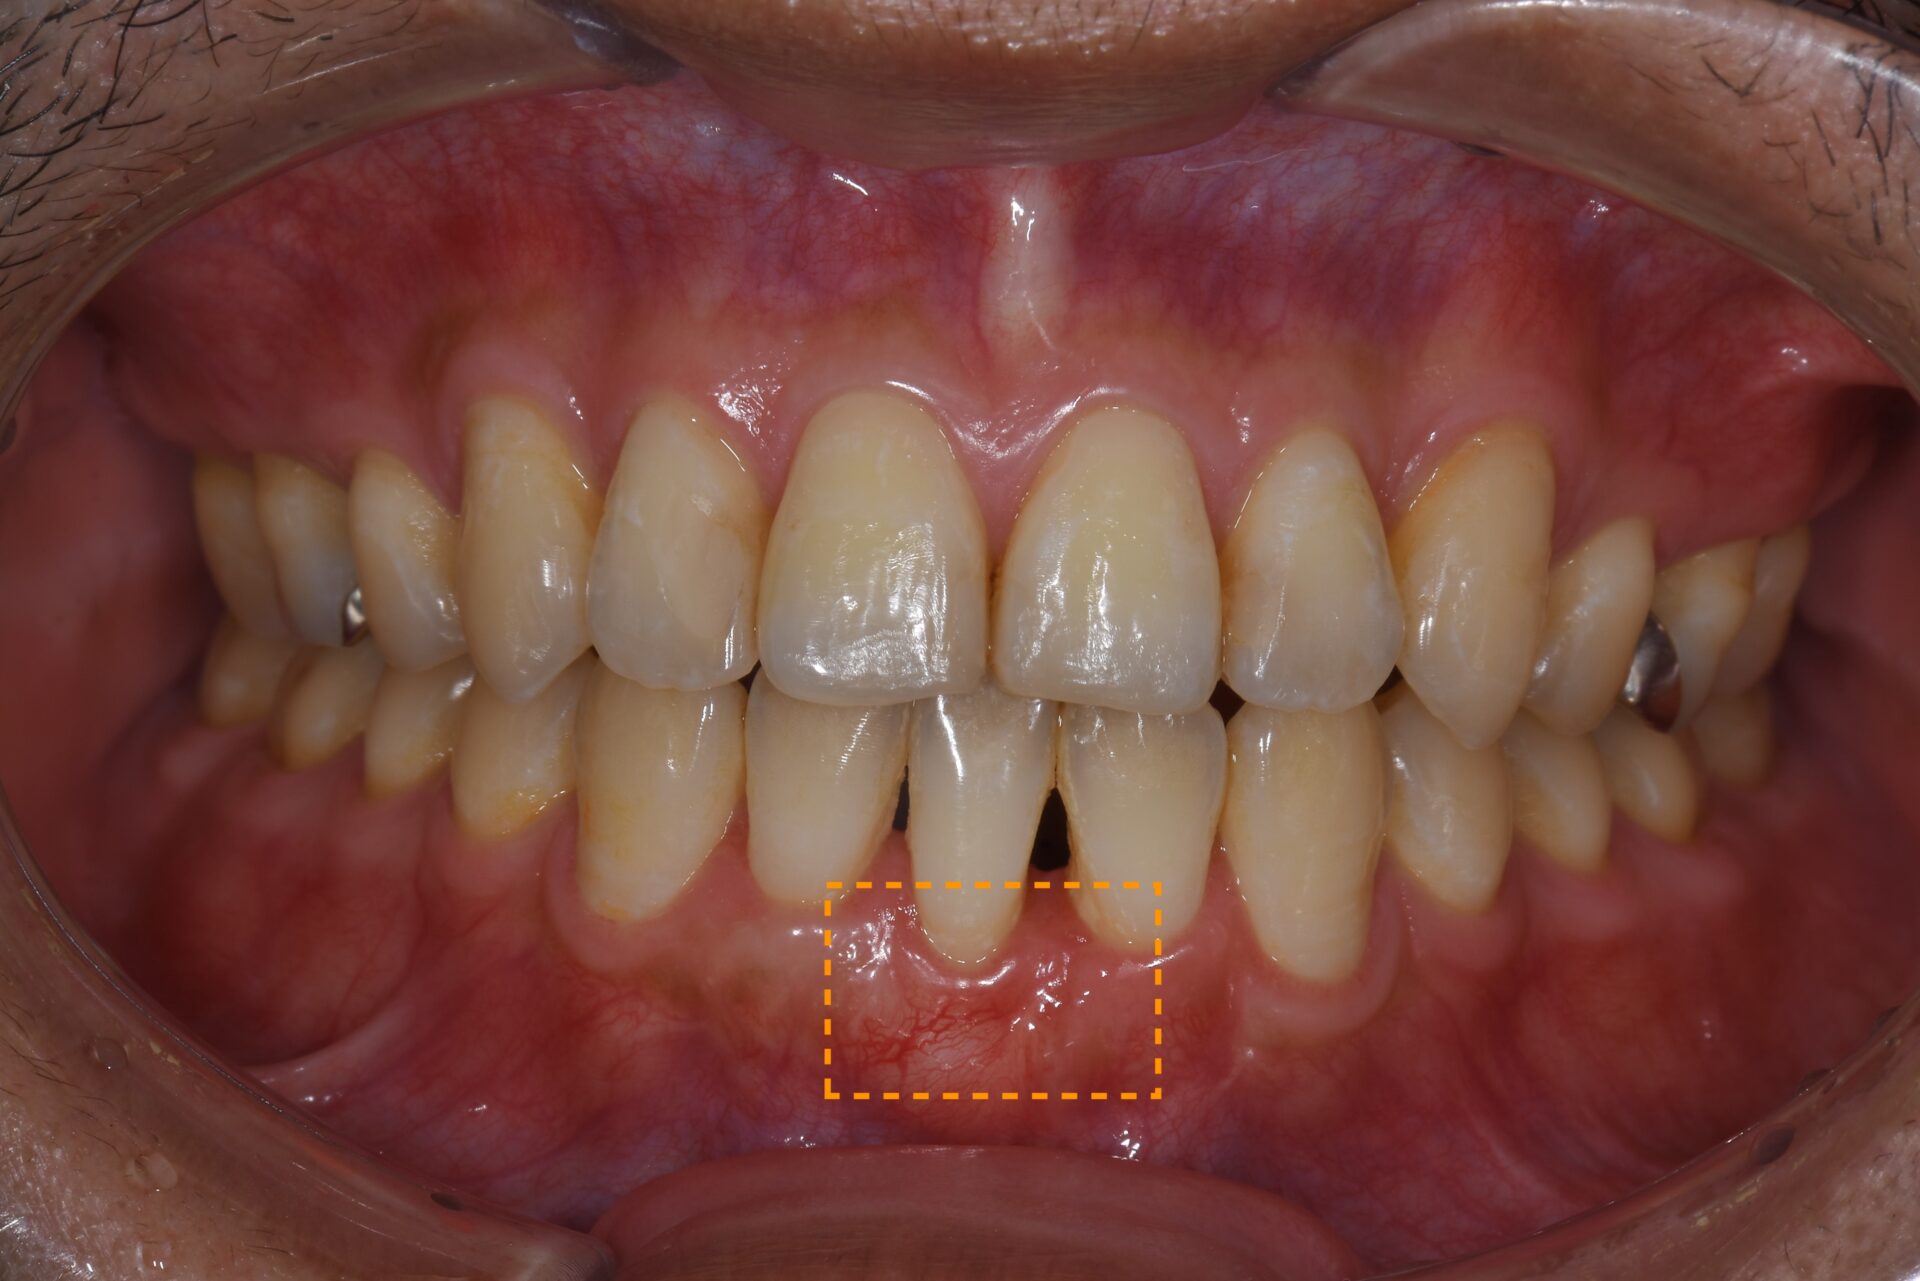

CTG(結合組織移植術) 臨床例①

前歯部の歯肉が薄く、付着歯肉が不足しているため、ブラッシングによる清掃が難しく炎症を繰り返していました。審美的にも不均衡が見られ、長期的な歯周組織の安定には改善が必要な状態でした。

術前